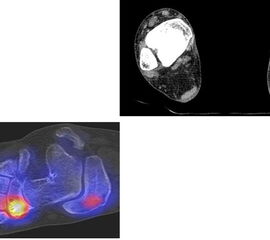

Abbildung 2.3.

Klärung bei Schmerzen im rechten OSG bei OCL an der medialen Talusschulter. Z. n. OSG-Distorsion vor 2 Jahren und Z. n. OSG-Fraktur / Syndesomosenruptur. Ausgedehnte OCL, hier jedoch kein erhöhter Knochenmetabolismus; lediglich Nachweis einer Stressreaktion im Bereich der Synchondrose eines Os trigonum als Schmerzursache.